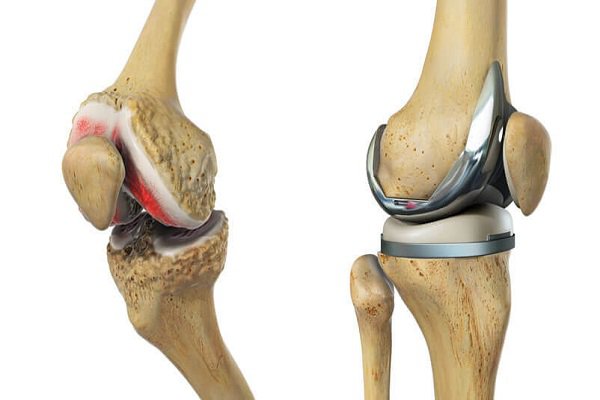

6. Thay khớp gối

- Thay khớp gối được áp dụng khi bệnh đã ở giai đoạn 3 hoặc 4, không thể điều trị bằng các phương pháp khác. Tuy nhiên đây là phẫu thuật lớn, chi phí bỏ ra rất cao. Thêm vào đó, tuổi thọ của khớp nhân tạo chỉ khoảng 10 - 15 năm, nên với bệnh nhân trẻ tuổi sẽ phải đối mặt với nguy cơ thay lại khớp nhiều lần. Do đó với phương pháp này, bệnh nhân sẽ được bác sĩ chuyên khoa khám xét và tư vấn kỹ lưỡng.